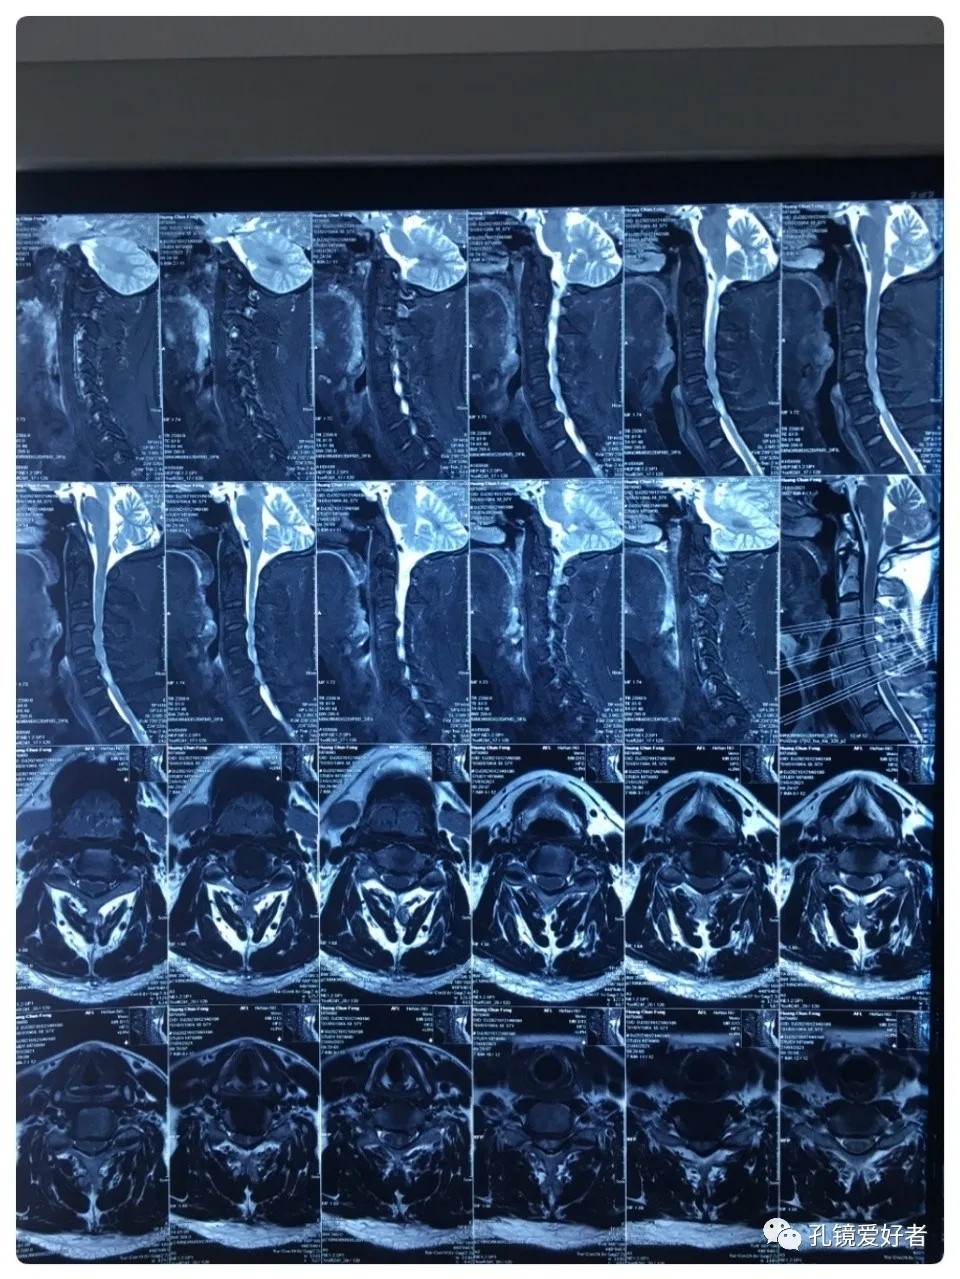

The patient's preoperative imaging data

Plain CT Scan of The Cervical Spine

CT imaging mainly focused on a plain scan of the cervical spine, and there is no scan on the intervertebral space.

Then let's look at MRI.

The MRI shows that the cervical stenosis is on C3-4, C5-6 and C6-7. Considering the patient's clinical symptoms, C5-6 and C6-7 are the main affected segments. So it’s advised that the patient undergo posterior cervical open-door laminoplasty. According to the patient, he had visited many hospitals before and received similar proposals of diagnosis and treatment- posterior cervical open-door laminoplasty. The reason he came to our hospital was that he wanted his surgery could be performed in a minimally invasive way. After considerable preoperative discussion with my colleagues and the patient, we decided to perform the minimally invasive endoscopic decompression for C5-6 and C6-7 double-segment stenosis through posterior approach (with the Delta system).